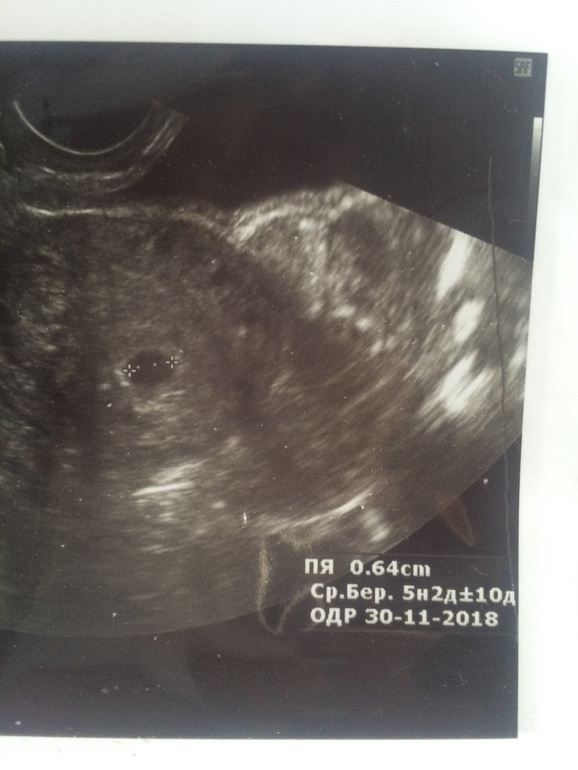

Страшно что-то. Болит слева, где была овуляция и жёлтое тело. На УЗИ насколько дней назад труба визуализировалась, н в ней ничего не нашли. И якобы даже увидели ПЯ в матке 2 мм.

Хгч позавчера на 18 дпо был 1590,7 растёт хорошо, на 16 дпо был 552, до этого 227.